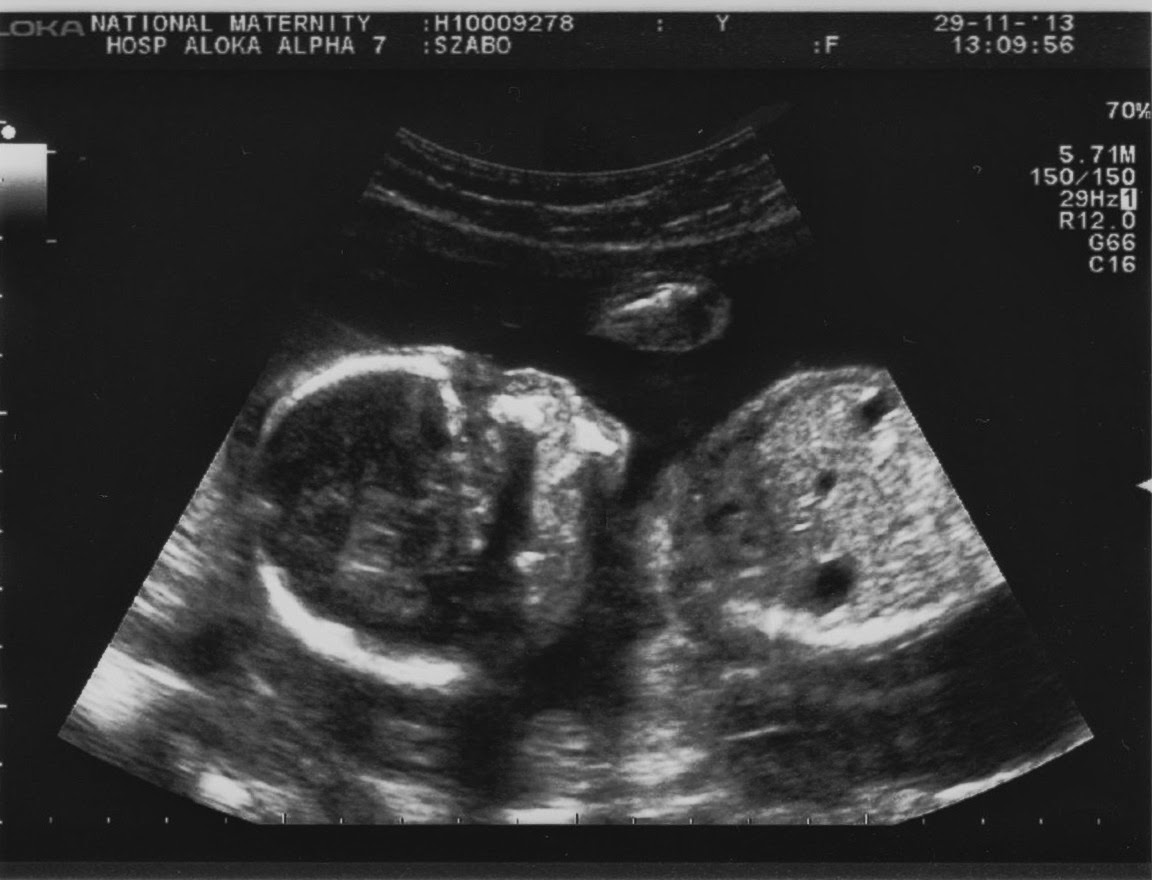

A végéről indítok: pénteken voltam a 20. heti genetikai ultrahangon. Ezt a vizsgálatot a kórházban az ún. "Fetal Assessment Department"-en végzik. Emlékszem Nórival annak idején a 17. héten csinálták meg ezt a vizsgálatot és ez volt az első kórházi látogatásunk vele.

Természetesen most is időpontra mentem és csak pár percet kellett várnom, azonnal szólítottak is. Egy nagyon kedves szonográfus végezte a hasi ultrahang vizsgálatot. Megnézte és megmérte a babát, a végtagjait, a belső szerveit. Mindent rendben talált. Viszont a méhlepény lent helyezkedik el. Elvileg, ahogy a baba feljebb vándorol majd, a lepény is magasabban helyezkedik majd el. Szóval emiatt most még nem kell aggódni. Nagyon valószínű, hogy ez változni fog. De ezt mindenképpen ellenőrizniük kell később, így ismét lesz majd egy részletes ultrahang, ugyanezen az osztályon, a 34. héten. Ha bármilyen aggasztó panaszom lenne addig (éles fájdalom, barna folyás, vagy vérzés), akkor azonnal be kell menni a kórházba (mondjuk ezekkel alapból azonnal rohannék be).

A vizsgálatok után megkérdezte a szonográfus, hogy szeretnénk-e tudni a baba nemét. Én most annyira nem tartottam ezt a dolgot fontosnak, de mivel Balázs mindenképpen szerette volna tudni, így igennel válaszoltam. A poszt végén, kiderül majd, hogy kislányt, vagy kisfiút várunk-e :) Csak egy kis türelem!